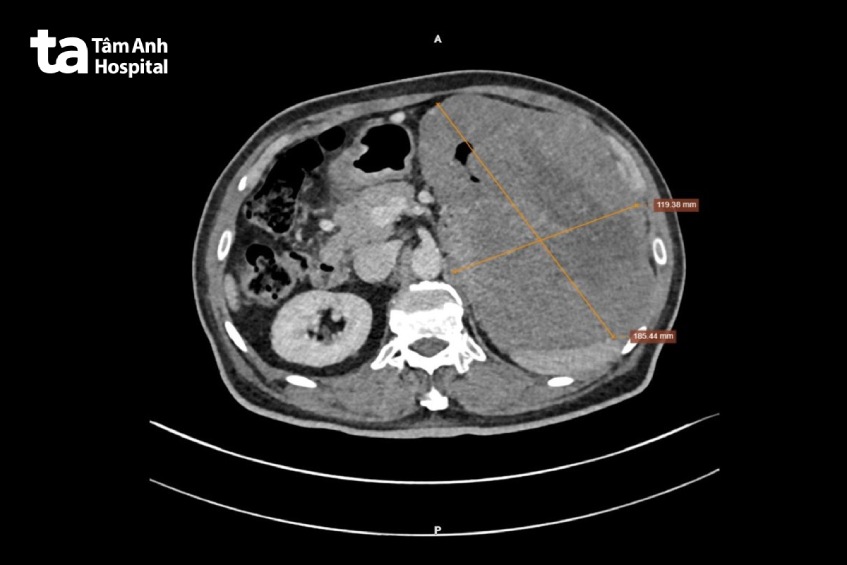

Kết quả nội soi cho thấy, người bệnh có khối u hơn 20 cm nằm ở vị trí phình vị dạ dày (phần cao nhất của dạ dày), đồng thời ghi nhận tình trạng hoại tử và xuất huyết bên trong. Kết quả chụp cắt lớp vi tính (CT) cũng cho thấy khối u xâm lấn vào gan và cơ hoành bên trái.

Kết quả giải phẫu bệnh của ông Khang chính xác là u mô đệm đường tiêu hóa (hay còn gọi là GIST – viết tắt là Gastrointestinal Stromal Tumor), với kích thước lớn hiếm thấy 30 x 20 cm, trọng lượng gần 2,5kg. Sau khi mổ, bệnh nhân cần theo dõi sức khỏe kỹ càng vì u này dễ tái phát. Đặc biệt, cần kết hợp dùng hóa trị (liệu pháp nhắm trúng đích) để điều trị triệt căn.